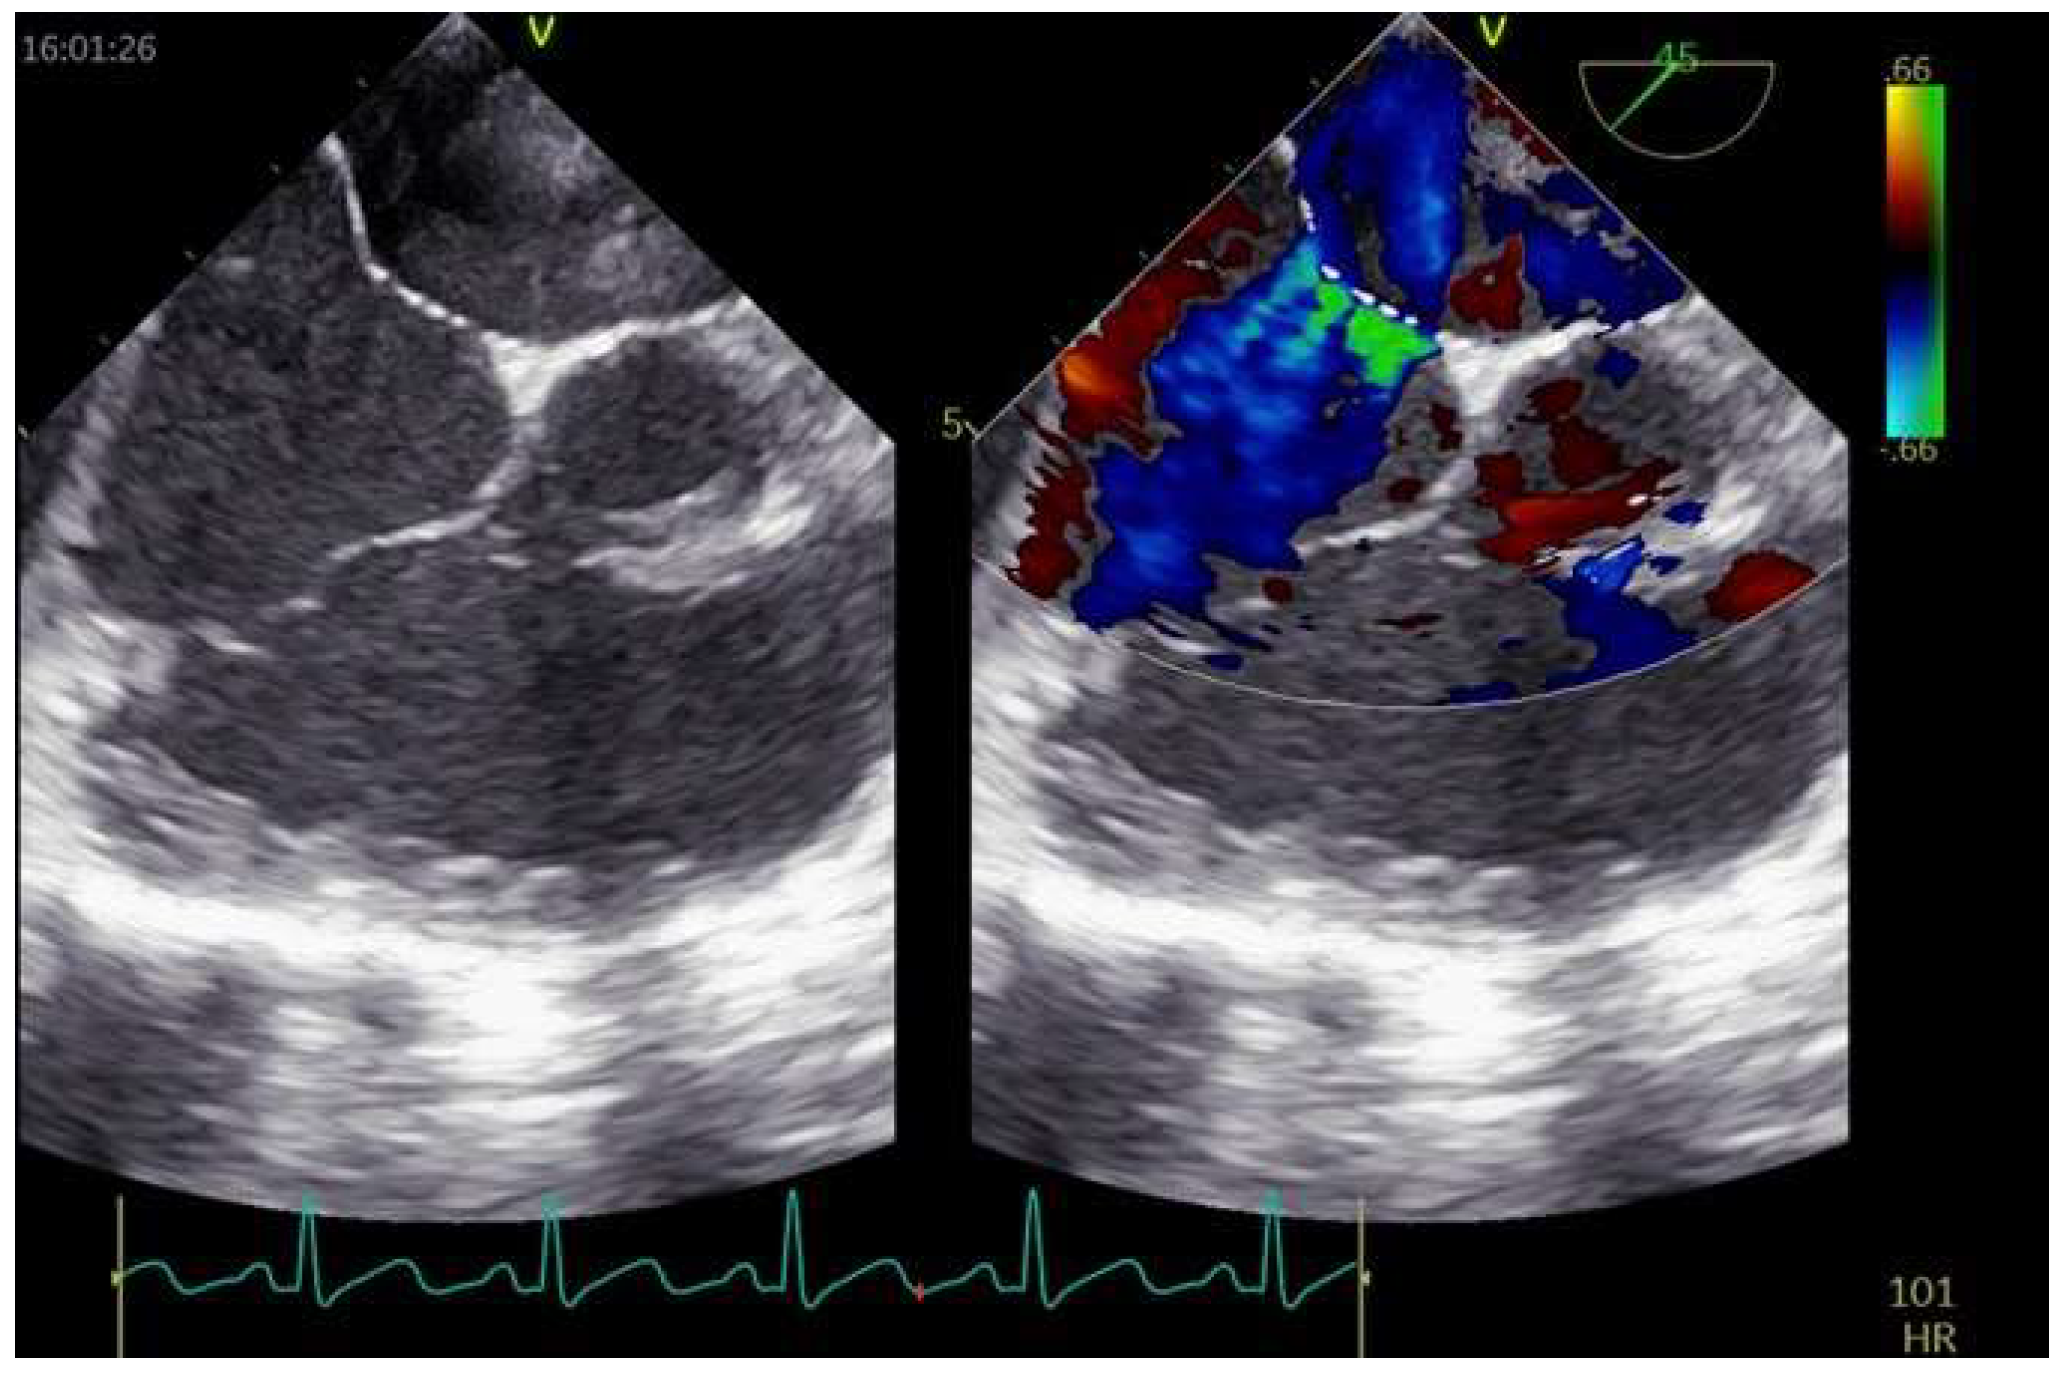

3.1. Aneurismatic Interatrial Septum

3.2. Multiple Accessory Fenestrations